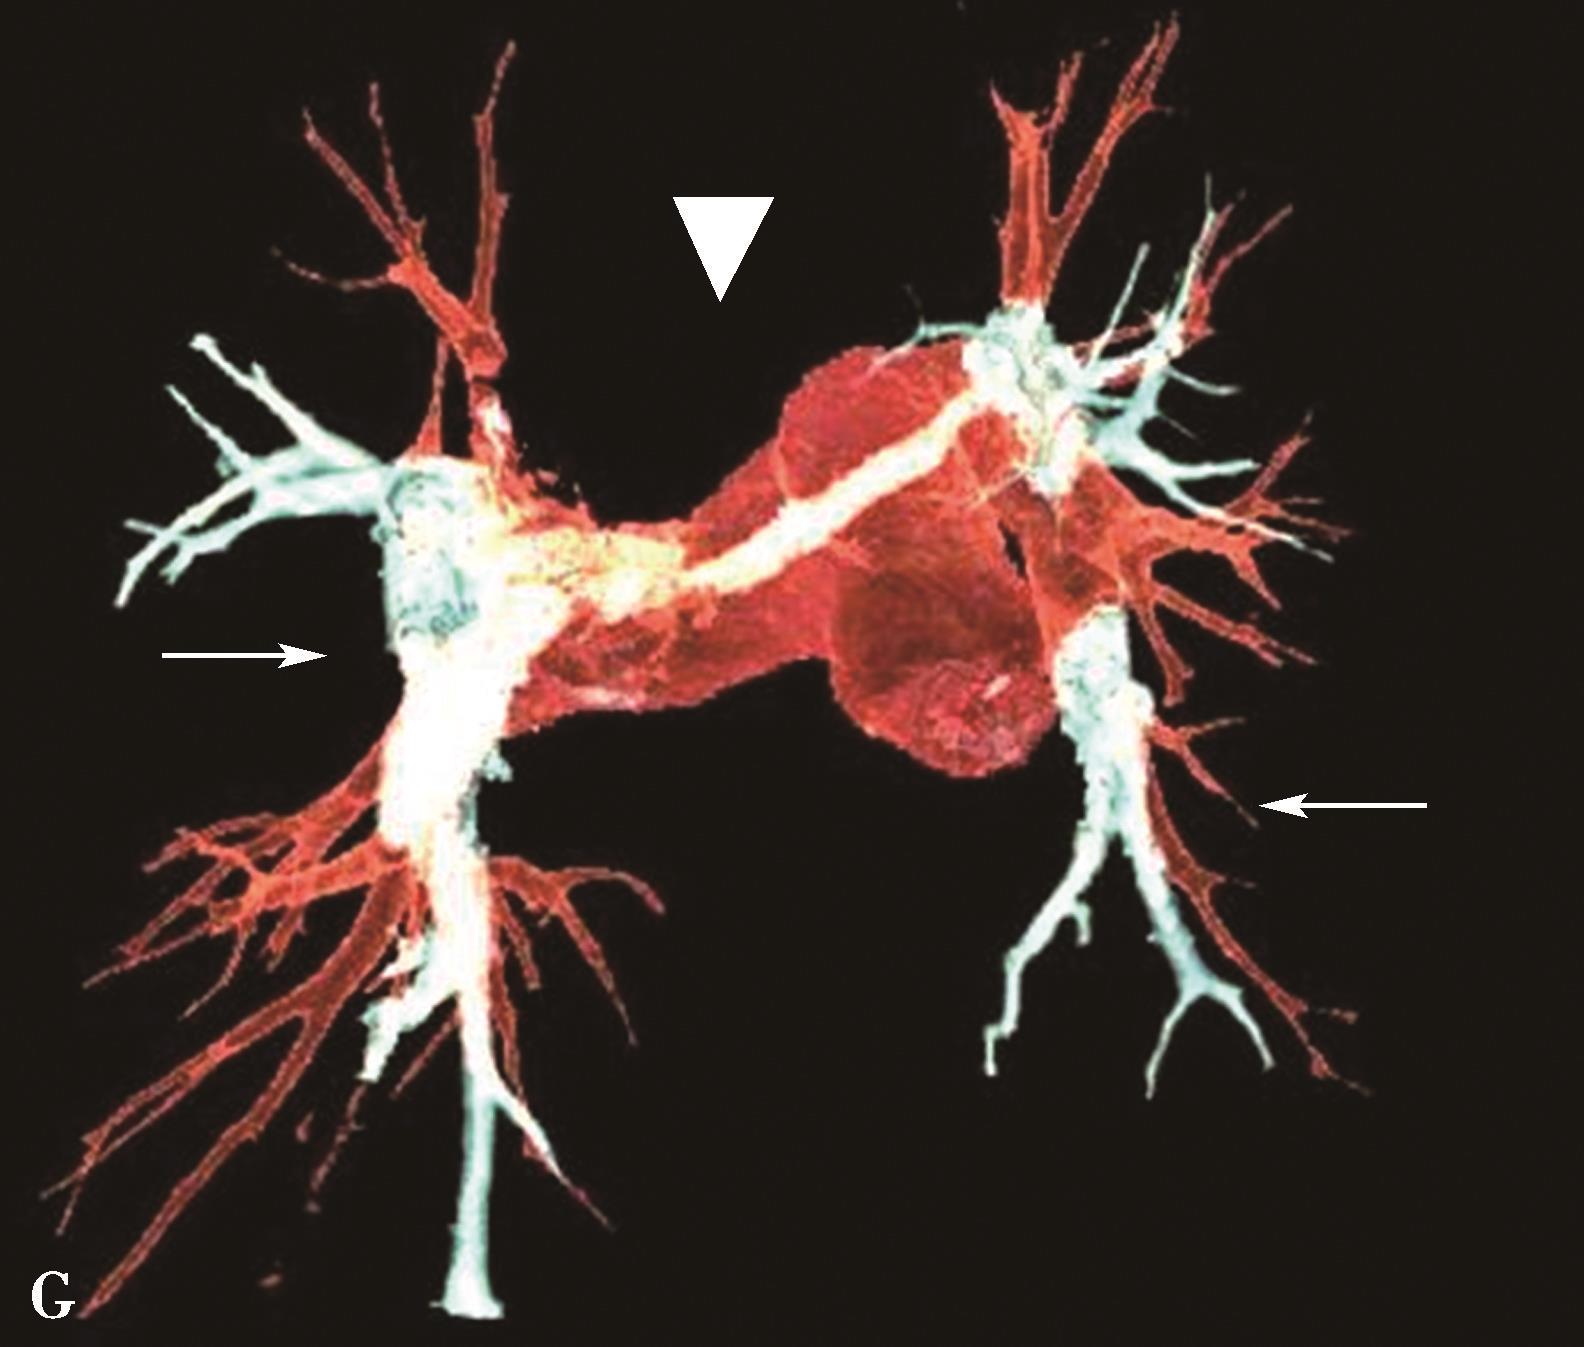

图8-4-12 慢性肺血栓栓塞性肺动脉高压(容积再现VR)

VR重建显示中心肺动脉明显扩张,远端分支明显纤细,迂曲、闭塞(↑)

各级血管可以表现为管腔完全闭塞,呈截断状;段及亚段血管由于血栓收缩引起血管直径的缩小,闭塞血管直径变细小(见图8-4-11B、 C, 图8-4-12)。

(2)肺动脉完全闭塞:

偏心性附壁血栓造成管壁呈波浪状增厚,以左-右肺动脉主干显示尤著(图8-4-11A↑)。

(1)中央肺动脉附壁型充盈缺损:

(二)慢性肺栓塞CT征象及诊断

慢性肺血栓栓塞的CT特征分为血管征象和肺实质征象。血管征象包括直接肺动脉征象(血栓机化的结果),肺动脉高压征象及体循环侧支的征象。